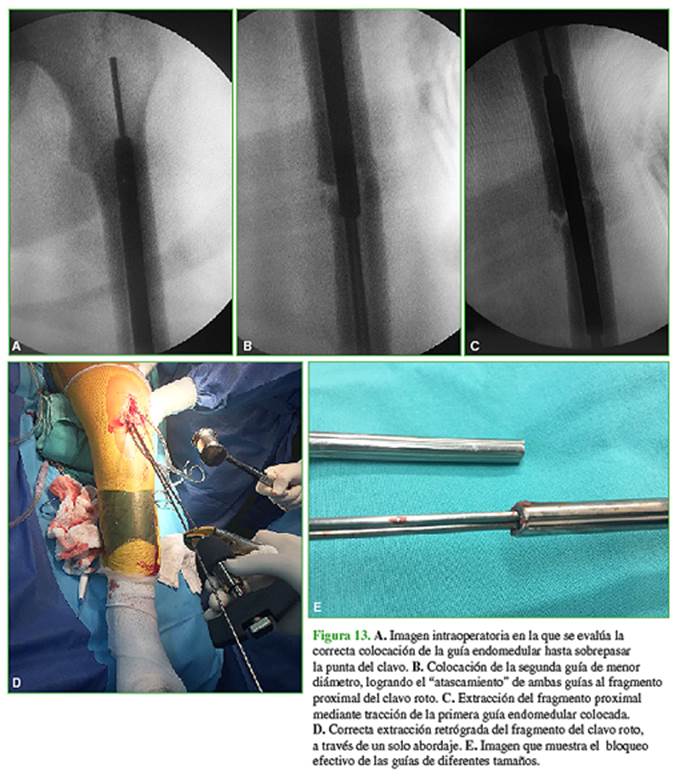

Se retiraron los bloqueos de forma percutánea y el fragmento distal del clavo por el abordaje rotuliano con el extractor específico. Luego se introdujo, en forma retrógrada, una guía endomedular no olivada a través del fragmento proximal del clavo hasta sobrepasar la punta del clavo aproximadamente 6 cm (Figura 13A).

El objetivo de esta técnica es introducir e impactar otra guía no olivada de menor diámetro hasta lograr el atascamiento de las dos guías (Figura 13B).

Una vez logrado el atascamiento, se traccionó de la primera guía que se colocó inicialmente, para luego extraer el fragmento proximal del clavo (Figura 13C), mediante un solo abordaje y sin complicaciones (Figuras 13D). En la Figura 13E, se observa el atascamiento eficaz de ambas guías.